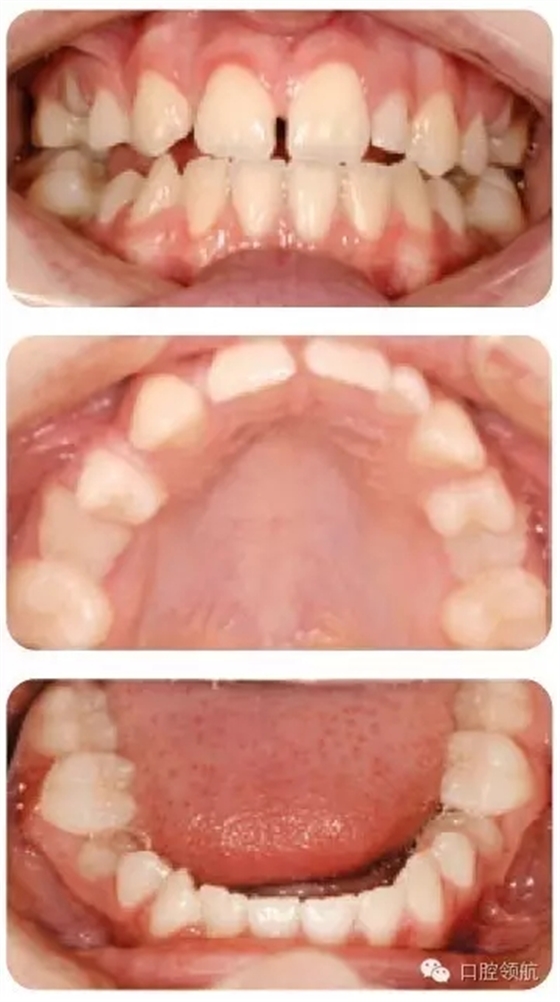

圖2.19中的III類病例有1顆過小的UL2, UR2和所有的第二前磨牙先天缺失,第二乳

磨牙滯留但預后不佳,治療方案是什么?

圖2.19

為了調(diào)整切牙III類關系,考慮擴開間隙修復UR2和過小的UL2。所有低的第二乳磨牙拔除并關閉間隙。